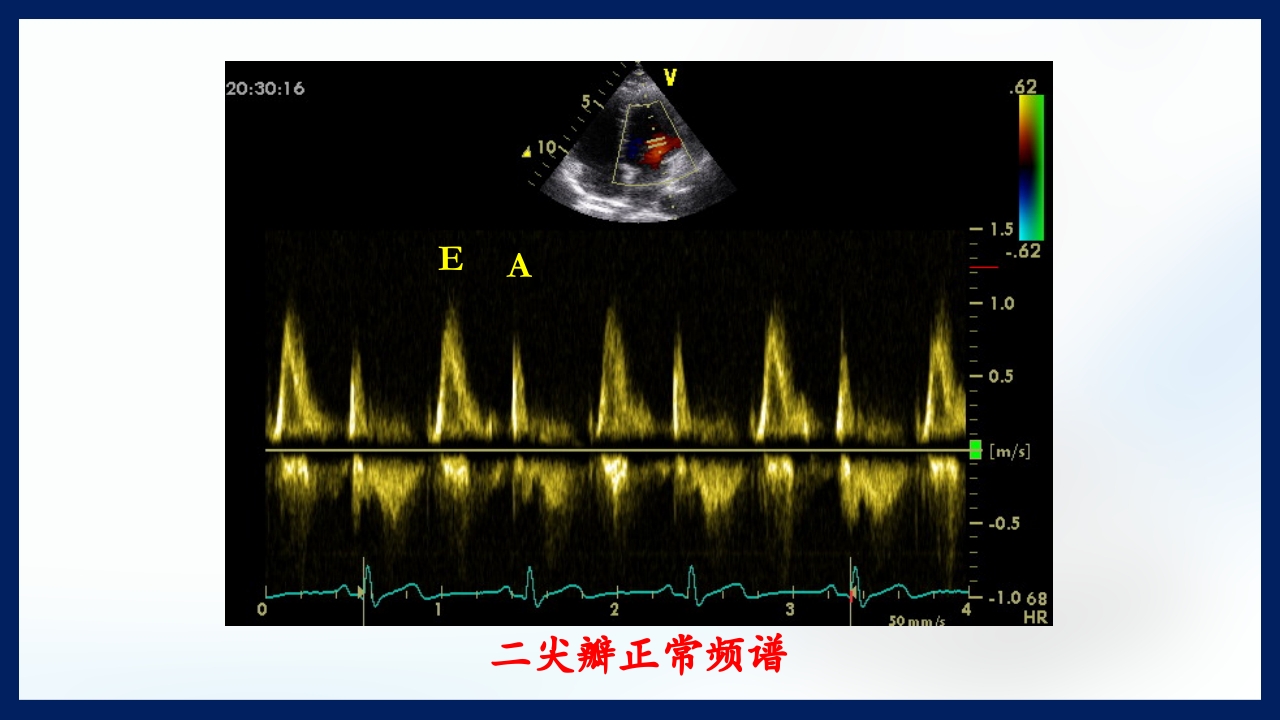

心 脏 瓣膜 医师:XXX 日期:20XX.XX.XX 讲授目的和要求 1 掌握二尖瓣和主动脉瓣膜病变的病理生理、临床表现及诊断方法。 熟悉二尖瓣和主动脉瓣膜病变的病因、鉴别诊断、并发症、治疗原则及 2 手术适应证。 3 了解瓣膜病的检查方法及治疗新进展。 心脏瓣膜病 是由于炎症、粘液样变性、退行性改变等原 因引起的单个或多个瓣膜结构的功能或结构异常,导致 瓣口狭窄及(或)关闭不全。二尖瓣最常受累,其次为 主动脉瓣。 (Rheumatic Heart Disease)简称风心病, 是风湿性炎症过程所致瓣膜损害,主要累及40岁以下人 群。 瓣膜粘液样变性和老年瓣膜钙化所致瓣膜病日渐增多。 3 瓣膜病分类 按病因分类: 风湿性、老年退行性、先天性、相对性 按受累部位和类型分: 二尖瓣狭窄、二尖瓣关闭...